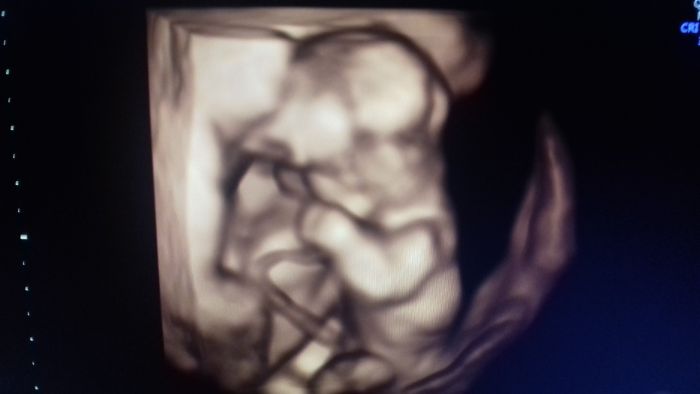

Tak už i my jsme konečně po screeningu. Morfologicky všechno vypadalo dobře, výsledky genetiky budou večer. Nakonec je všechno trochu jinak, než jsme čekali - prcci mají společnou placentu, takže jsou to jednovaječná mo-bi dvojčátka. Bohužel je tím všechno komplikovanější, nezbývá než doufat, že placenta vydrží až do 36. týdne, kdy je nejzazší termín porodu. Moc jsem se těšila na holčičku, když už doma jednoho kluka máme, ale vypadá to na čistě mužskou smečku :)

[1140029] Ahoj Nionne, dalsi dva chlapecci,to je uzasne,i kdyz chapu,zes doufala v holcicku

Hlavne at jsou mrnousci v poradku,drzim vsechny palce.Uz dvojcatka jsou samo o sobe nadhera